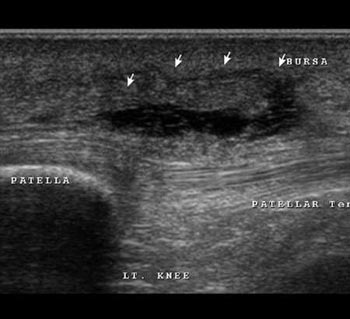

Prepatellar bursitis

Prepatellar bursitis is seen anterior to patellar tendon.